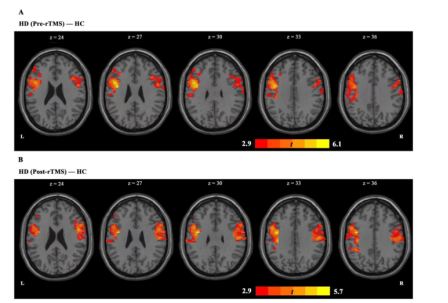

In 2022,The team of Longxiao Wei of Tangdu Hospital of the Air Force Military Medical University uses the transcranial magnetic stimulation (TMS) device for sale (M-100 Ultimate, YINGCHI, Shen Zhen, China) to analyze the functional connections between the default mode network (DMN) and other brain networks of 30 heroin addicts before and after 7 times of transcranial magnetic stimulation. Studies have shown that repetitive transcranial magnetic stimulation can regulate the functional connection between the default functional network and the executive control network, and the change of functional connection between the left inferior parietal lobule and the left middle frontal gyrus may play an important role in reducing drug cue-induced craving.[12]